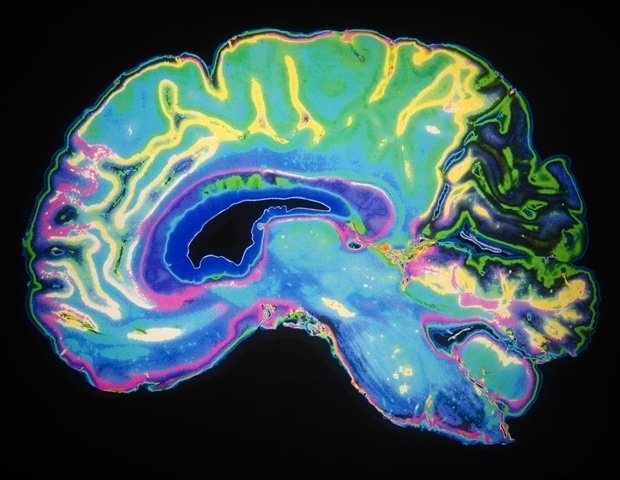

The internal compass, known as the head direction system, is a network of brain cells that tracks which way we are facing as we move. It also connects the hippocampus, the brain’s memory center, with other parts of the brain.

The researchers tracked the same brain cells in mice over several months using a small head-mounted microscope. They found that even when the hippocampus was reorganized, the head direction system remained structurally intact.

These findings reveal a surprising contrast. Although the hippocampus may reorganize its activity over time, the head direction system provides a very stable basis for interpreting spatial information. ”